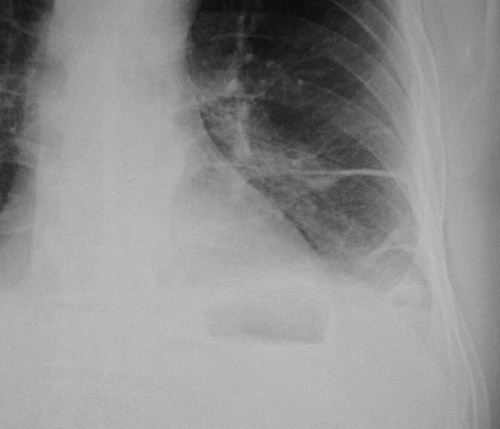

The magnified view of the chest radiograph in PA view on the right above demonstrates fluid in the major fissure in a patient with left heart failure. The magnified view of the fluid in the major fissure on the left is seen below.